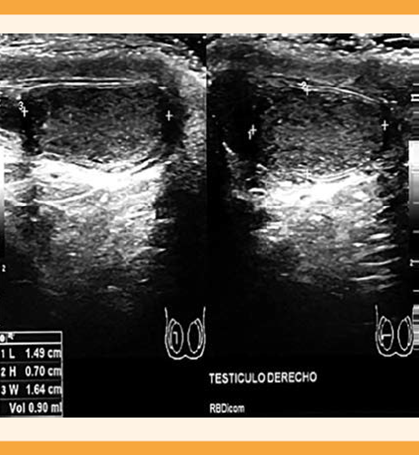

A la pareja se le practicaron estudios de laboratorio y gabinete. A la paciente se le solicitó progesterona, prolactina y hormona estimulante de tiroides (TSH) tomados en fase lútea media que indicaron ovulación, prolactinemia normal y eutiroidismo. La histerosalpingografía reportó que la cavidad uterina se encontraba normal y las salpinges permeables. Al varón se le solicitó un análisis seminal que reportó azoospermia; se repitió a las 2 semanas y nuevamente se encontró azoospermia, con un espermocultivo en búsqueda de Chlamydia y Mycoplasma que se reportó negativo. El semen se centrifugó para confirmar el diagnóstico de azoospermia. Los siguientes estudios se enfocaron en conocer la causa de la azoospermia y poder iniciar un tratamiento adecuado. El ultrasonido testicular reportó ambos testículos disminuidos de tamaño con contornos regulares, derecho 1.4 x 0.7 x 1.6 cm con volumen de 0.9 cc (Figura 1), izquierdo 1.6 x 1.5 x 0.8 cm con volumen de 1.1 cc (Figura 2). Epidídimos hipoecoicos con un quiste en la cabeza, en el lado derecho de 1.7 mm. Ambos cordones espermáticas sin flujo Doppler y disminución en su ecogenicidad.

Figura 1 Imagen de ultrasonido testicular derecho, se observan los cortes longitudinal y transversal y el volumen testicular con hipotrofia.